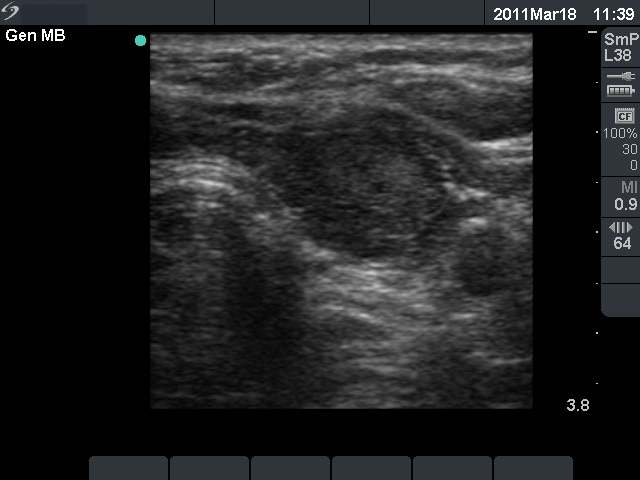

Ultrasonography: revealed hypoechogenic inhomogeneous thyroids with an echonormal circumscribed lesion in the left lobe corresponding to a secondary lobule.

Combined ultrasonographic-cytological diagnosis: benign Hashimoto's thyroiditis.